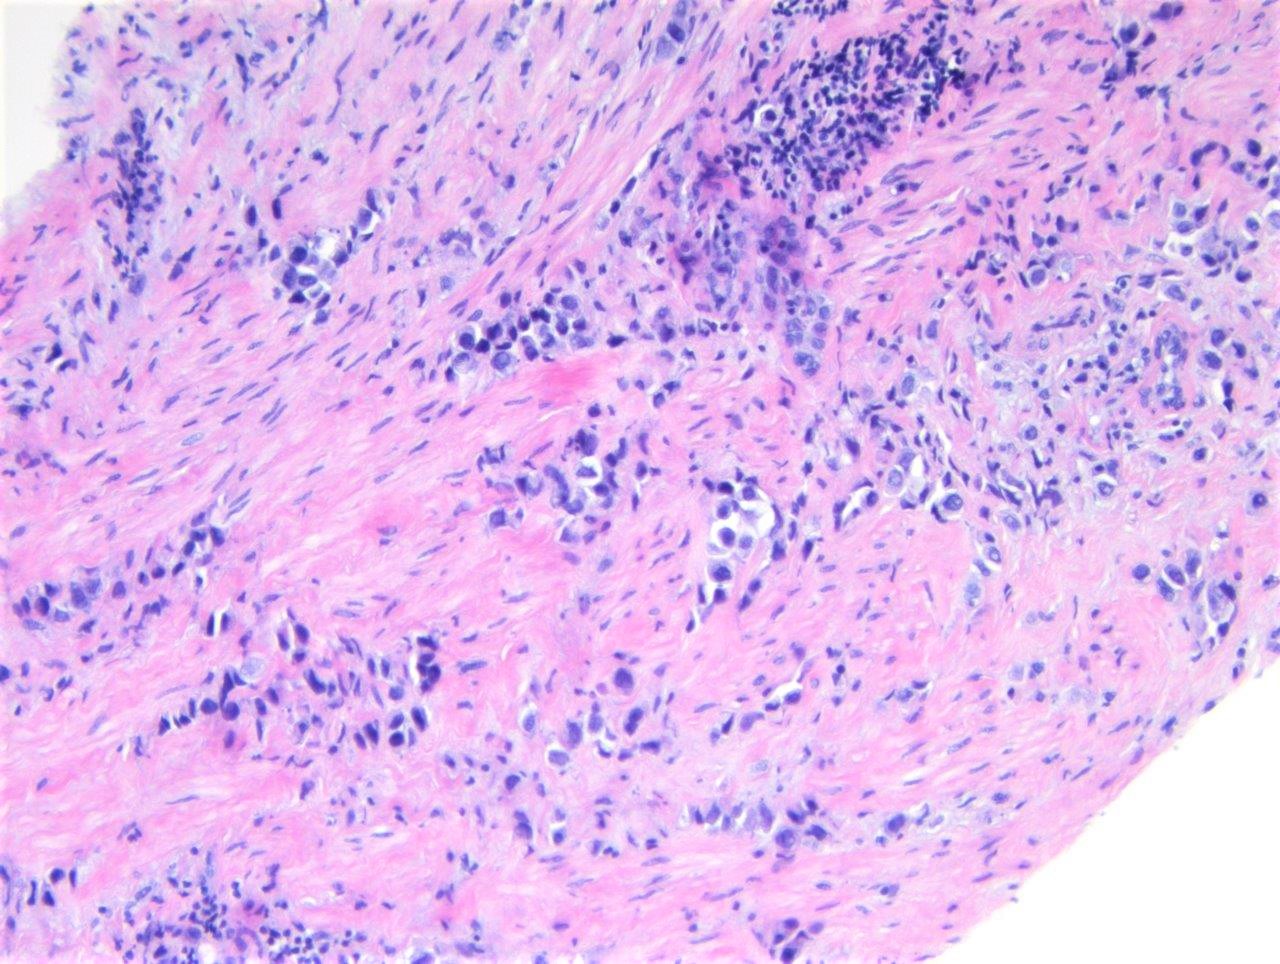

Microscopic (histologic) description

- Discohesive single cells with eccentrically placed nuclei and abundant eosinophilic cytoplasm

- Often deeply infiltrative but with minimal stromal reaction (Eur Urol Focus 2020;6:653)

- Further subclassified into classic, pleomorphic and desmoplastic subtypes:

- Classic: signet ring-like morphology, singly scattered and discohesive in loose aggregates forming cords (Hum Pathol 2019;90:27)

- Pleomorphic: similar to classic but with pleomorphic nuclei and more atypia; can be rhabdoid and bizarre appearing (Hum Pathol 2019;90:27)

- Desmoplastic: plasmacytoid neoplastic cells with a surrounding desmoplastic stromal response (Hum Pathol 2019;90:27)

- Associated with sarcomatoid variant in 31% of cases (Hum Pathol 2019;90:27)

- Often mixed with other histologic subtypes; in 1 case series, 53% of PUC had mixed histologic subtypes (Am J Clin Pathol 2017;147:500)

- Despite resemblance to signet ring carcinoma cells, notably lack extracellular mucin, contrasting to signet ring adenocarcinoma (Acta Cytol 1991;35:277, Am J Surg Pathol 1991;15:569)

Microscopic (histologic) images

Contributed by Timothy Isaac Miller, M.D., M.A., Nicole K. Andeen, M.D. and Maria Tretiakova, M.D., Ph.D.

Contributed by Lisa Han, M.D. and Ricardo Lastra, M.D. (Case #510)